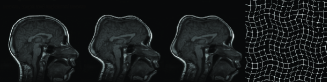

In Figure 9, three example registration results of randomly and nonlinearly warped images are shown. Capturing signal intensity variations during registration process with intensity standardization method leads to assesment of visual comparision of registered source and target images with warping grid. Evaluation of the registration results is summarized in Table-2. The table shows that large and small scale deformations are captured accurately on the standard intensity scale. Resulting images have fixed intensity meanings even there is large intensity variations initially.

Another method to evaluate proposed registration method is visual examination of checkerboard images. Figure 10 shows an elastic registration example together with checkerboard image illustrating how well the image pair is registered. Checkerboard image includes white and black squares corresponding to intensity values taken from the registered source and the target image respectively. Our overall observation from experimental results is that multiresolution elastic registration on standard intensity scale can capture both local and global deformations with high accuracy.